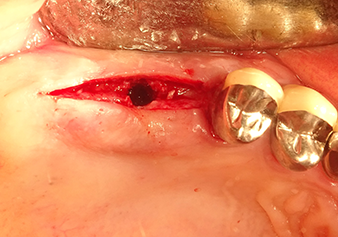

Après un contrôle intermédiaire (Fig. 4), une étape de préparation ultérieure est exécutée (Fig. 5). Puis on utilise l’insert Z35P hydraulique pour relever la membrane vers la position souhaitée (Fig. 6 et 7). Ensuite, une préparation piézochirurgicale supplémentaire est pratiquée sur le site implantaire, en utilisant pour terminer un burin rotatif et une fraise à épaulement jusqu’à 4,8 mm de diamètre d'implant. Avant l’insertion de l'implant, le matériau d’augmentation (taille de particules env. 0,8-1,6 mm) est introduit sous la membrane de Schneider (Fig. 8).